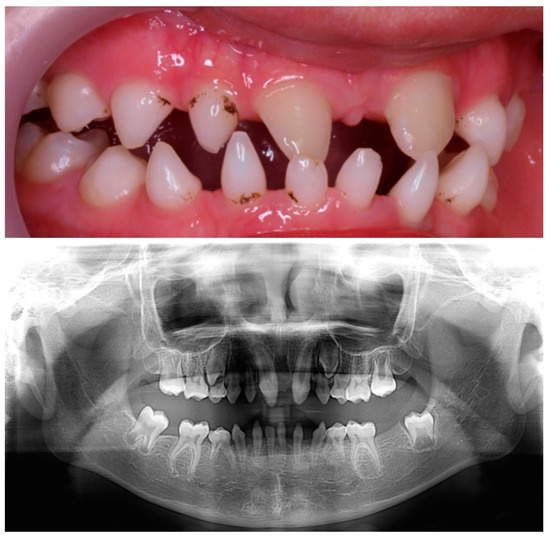

Figure 1.

Presence of conical anterior temporary teeth. Absence of the left lateral maxillary incisor and the maxillary and mandibular second molars.

Figure 2.

Clinical and radiographical findings at 6 years old.

We present the case of an 11-year-old Chinese boy who was referred to the dentist at the age of 23 months. In the first visit, it was noted that the boy was missing the left maxillary lateral incisor (6.2) and the maxillary and mandibular second molars (5.5, 6.5, 7.5, 8.5) and that he had conical-shaped anterior teeth (5.2, 7.2, 7.1, 8.1, 8.2) (Figure 1). The clinical examination results of his hair, eyes, eyebrows, nails, fingers, and skin were normal, except for dryness of the skin. His weight and height were at the 10th percentile. According to the parents, dental eruption was age-appropriate, at around 6 months of age. Psychomotor development was normal, and there were no previous episodes of fever or other significant pathologies. He was born at term after an uncomplicated pregnancy. The parents were nonconsanguineous. The paternal grandparents came from Daxue, China, and the maternal grandparents from Yuhu Village, China. The paternal grandparents came from Daxue, China, and the maternal grandparents from Yuhu Village, China.

In a new dental visit, at the age of 6 years, an orthopantomography was performed, where multiple agenesis was observed in both the primary and permanent dentition. Given that more than six permanent teeth were missing, it was labelled as oligodontia [14] (Figure 2). He also had a comprehensive phenotypic evaluation, and a genetic study was performed.